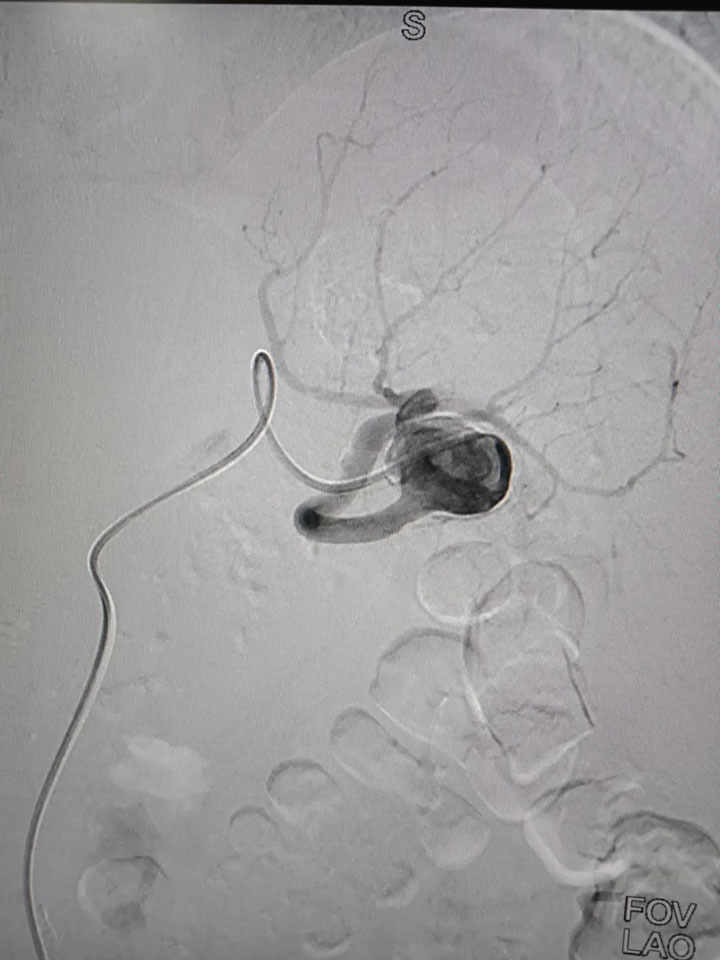

经过完善的术前评估,普外科邀请集团普外医疗中心血管外科桂锐主任、胡玉东主任,仅在股动脉做一2cm小切口,通过一根导丝,精准定位瘤体位置,将弹簧圈置入瘤腔,顺利完成手术。

“患者的脾动脉瘤直径较大,属于囊状动脉瘤,瘤体向动脉一侧偏心性扩张,这类口袋状的动脉瘤,破裂的风险更高,占总数的75%。患者发现及时,手术顺利,很幸运。”胡玉东主任说。

广济普外科健康科普:脾动脉瘤起病极为隐匿,多无明显症状,偶有左上腹不适感,可向左肩胛放射。一旦出现明显左上腹或左季肋区疼痛、恶心、呕吐等症状,往往预示动脉瘤先兆破裂。需特别指出的是:脾动脉瘤在妊娠期更容易发生破裂,并且其死亡率可上升至高达 70%。目前腔内介入治疗为脾动脉瘤的首选治疗方案。脾动脉瘤的检查方法有很多,如:彩色多普勒超声、CTA、DSA;DSA 是诊断内脏动脉瘤的「 金标准 」。